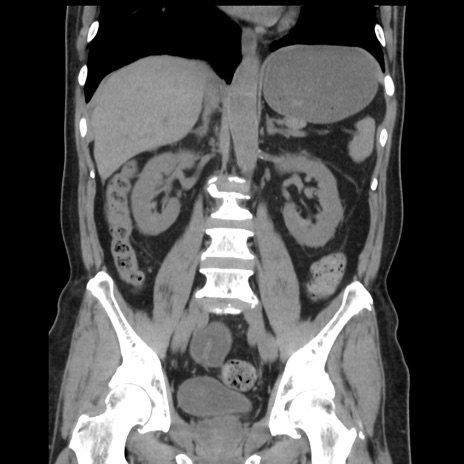

症例16(冠状断像)

【症例】 70歳代男性

【主訴】 腹痛、嘔吐

【現病歴】 約1ヶ月前より間欠的に腹痛と嘔吐あり、当院消化器内科を受診したところCTで多発する肝臓のLDAを指摘され、精査中であった。以降は消化器症状は安定していたが、2日前より嘔気と腹痛があり、同日より排便・排ガスが消失した。改善認めず、 本日、救急外来を受診した。

【既往歴】 大腸ポリープ切除後。

【身体所見】意識清明・会話良好、BT 36.3℃、BP 127/80mmHg、 P 80bpm、腹部:膨満あり、平坦・軟、上腹部正中および下腹部正中に圧痛あり、反跳痛なし、筋性防御なし。

【データ】WBC 7200、CRP 0.77